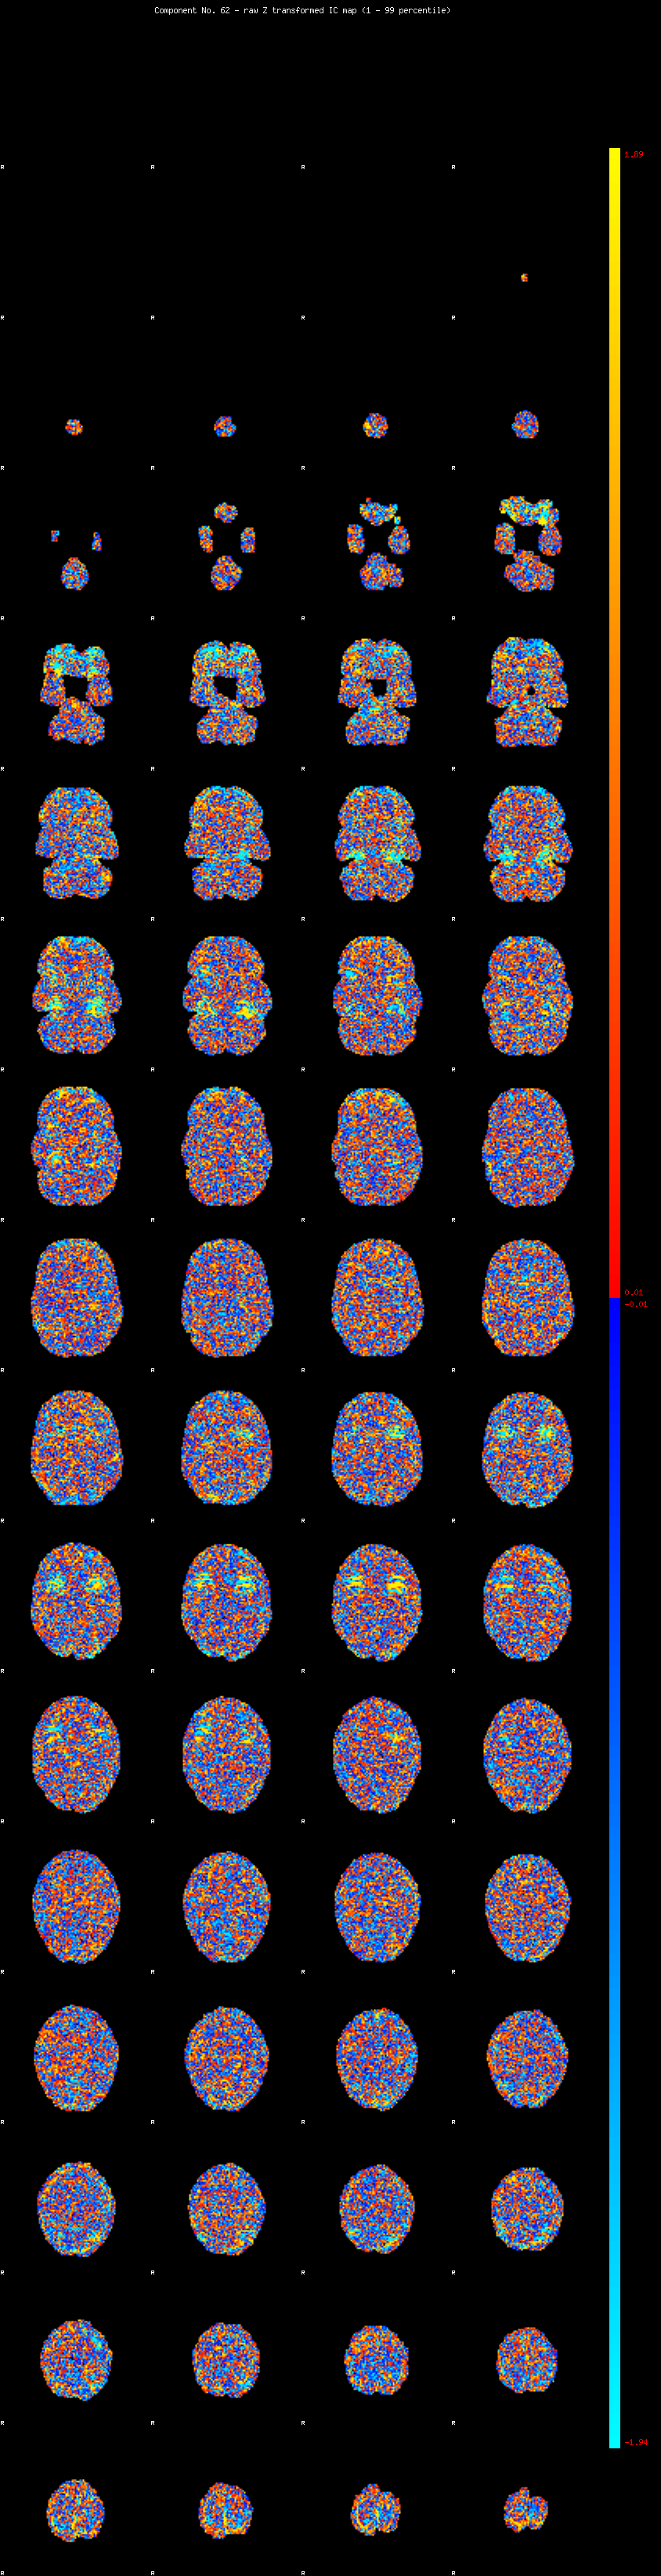

IC_62 Mixture Model fit

Means : -0.000000 2.322724 -2.457706

Vars : 1.000000 1.572782 1.980694

Prop. : 0.951940 0.022723 0.025337